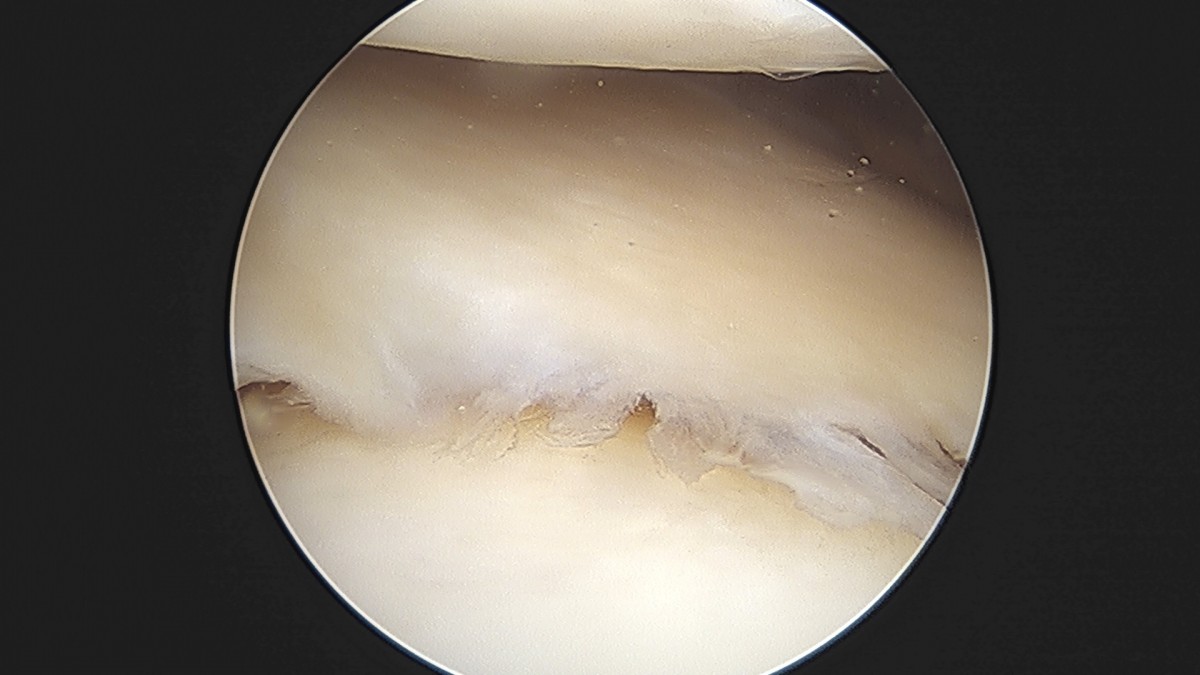

이재상원장님 무릎 반월상 연골판 절제술 박강O 환자

작성자 최고관리자 댓글 0건 조회 381회 작성일 25-09-16 15:47